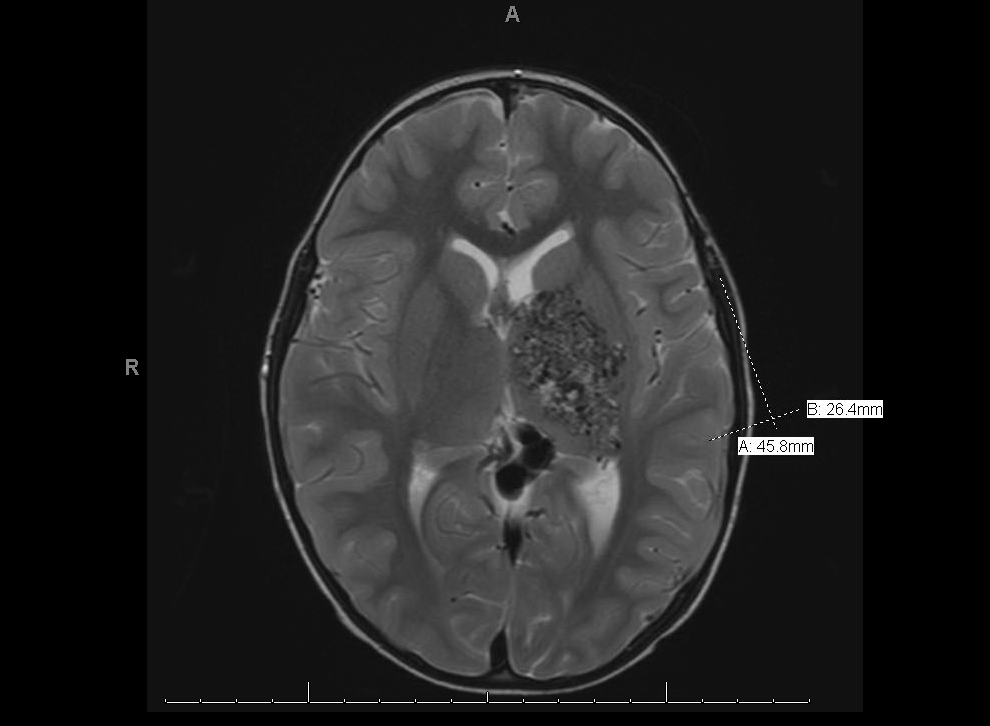

T2-weighted MRI of the brain with contrast displaying large left arteriovenous malformation, centered on the posterior limb of the internal capsule with involvement of the left basal ganglia and thalamus.

headaches and a two-day history of left eye redness and tearing. He denied blurriness, eye pain, or purulent discharge. On review of systems, he did not have any upper respiratory infection-like symptoms. His past medical history was significant for a large left basal ganglia arteriovenous malformation (Figure 1) causing mild right-sided weakness; prior evaluation by neurosurgeons deemed the malformation inoperable due to its large size and risk of significant morbidity associated with surgery.

The presence of this patient’s retinal and intracranial arteriovenous malformations is consistent with a diagnosis of Wyburn-Mason syndrome. The patient’s left eye injection is probably a red herring and more likely related to a conjunctivitis than venous outflow obstruction or a carotid-cavernous fistula; the latter typically manifests as a sectoral region of injection with individual dilated vessels rather than this patient’s diffuse, mild injection associated with follicles. Additionally, the proptosis frequently seen with a carotid-cavernous fistula is not clinically present here. Neuroimaging of the patient’s brain and orbits revealed normal orbital vasculature.

When a patient is found to have a retinal AVM, neuroimaging with either magnetic resonance imaging (MRI) or computed tomography (CT) of the brain and orbit in addition to magnetic resonance angiography (MRA) should be considered because of the risk of associated systemic AVMs. It is critical to note that some CNS malformations are potentially lethal. Intracranial AVMs can also cause vision loss secondary to stroke or disruption of the anterior visual pathway if the lesions violate the optic tracts or radiations. Neurologic complications include cranial nerve palsies, hemianopia, hemiparesis, and convulsions.[2] AVMs can also cause significant mortality if they lead to intracerebral or subarachnoid hemorrhage.[4] Patients with cerebral AVMs are monitored closely throughout life since cerebral AVMs have the potential to morph over time due to hemodynamic factors, sometimes evolving into spontaneous thrombosis or hemorrhage. Retinal AVMs possess the same potential for spontaneous changes due to turbulent flow and high intravascular pressure which can lead to vessel wall damage and subsequent thrombosis and occlusion.[8] Both retinal and intracerebral AVMs carry low risk for neoplastic transformation.[12]